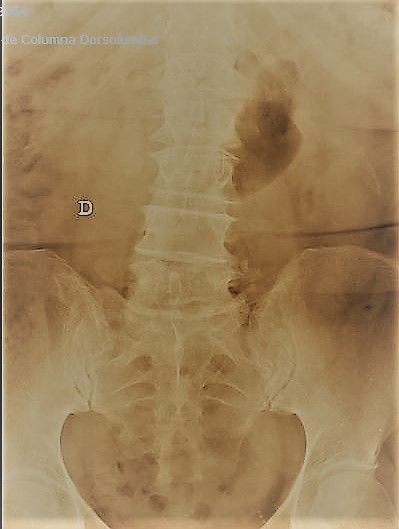

–Fracturas vertebrales: Frecuentes sobre todo en la columna dorso-lumbar, pueden aparecer como consecuencia de mecanismos muy diversos; desde grandes traumatismos, en cuyo caso su tratamiento puede estar condicionado por la presencia de otras lesiones, o bien tras traumatismos banales o incluso de forma espontánea, sin traumatismo alguno. Estos últimos casos definen las «fracturas patológicas» en las que es preciso buscar una causa subyacente estructural o sistémica que haya provocado el debilitamiento óseo. Esta situación es especialmente frecuente en mujeres tras la menopausia debido al desarrollo de osteoporosis. Estos casos precisan iniciar un tratamiento para compensar la desmineralizacón ósea. El tratamiento de las fracturas depende fundamentalmente del grado de deformidad asociado, la afectación de ligamentos (ambos aspectos definen la presencia o no de inestabilidad) y el que exista o no una lesión neurológica. En caso de fracturas estables sin déficit neurológico se emplea una ortesis mientras que en presencia de inestabilidad o afectación neurológica debe valorarse la cirugía.

Patología traumática de la columna vertebral: Está representada por las fracturas vertebrales. Este fenomeno cada vez más frecuente debido a la alta prevalencia de la osteoporosis va a dar lugar a la ruptura de los elementos óseos que conforman las vértebras, a veces motivada por traumatismos menores, lo que además de dolor importante puede generar fenómenos de inestabilidad y/o lesiones neurológicas debidas a la compresión de la médula espinal o las raíces nerviosas.